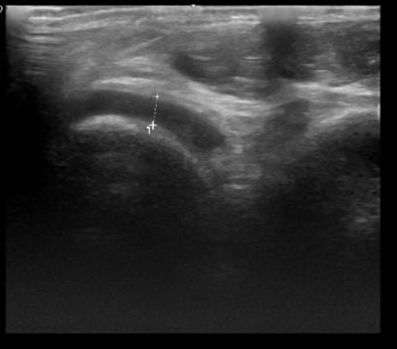

Từ triệu chứng lâm sàng, bệnh nhân được chẩn đoán sơ bộ: theo dõi gút cấp/béo phì độ II và được chỉ định thực hiện xét nghiệm máu, chẩn đoán hình ảnh chuyên sâu. Kết quả xét nghiệm cho thấy anh H có chỉ số acid uric máu tăng cao; rối loạn chuyển hóa lipid máu (tăng cholesterol và triglycerid); siêu âm khớp cổ chân trái có tràn dịch khớp; siêu âm ổ bụng cho thấy gan nhiễm mỡ độ II; có polyp túi mật.